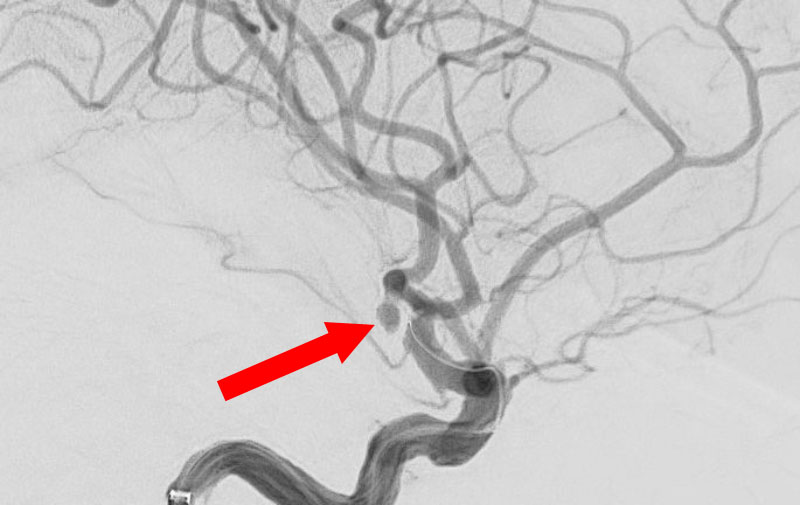

No.1593 手術前